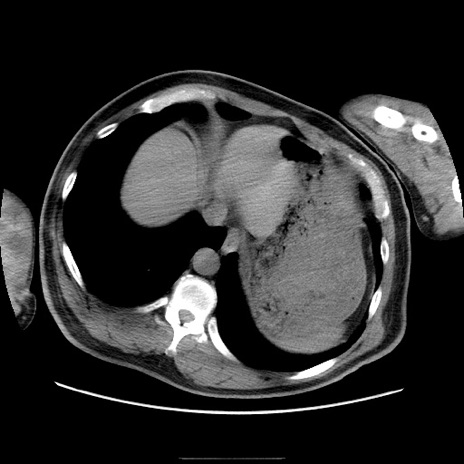

症例22(横断像)

【症例】50歳代男性

【主訴】腹痛

【現病歴】AVMからの被殻出血のため回復期リハ病棟入院中。 本日午後3時頃急に下腹部痛が出現した。

【既往歴】AVM、被殻出血、虫垂炎、高血圧

【身体所見】意識晴明、左半身不全麻痺、会話の理解は良好、36.5°C、腹部:膨隆、全体に板状硬、下腹部正中に圧痛点あり、反跳痛-、筋性防御不明、右下腹部にope scar

【データ】WBC 9400、CRP 0.06